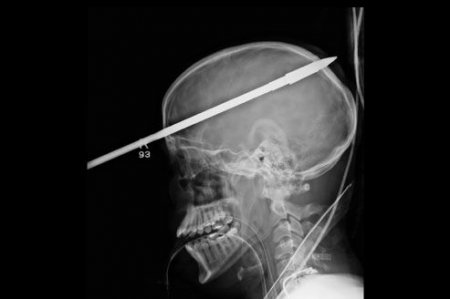

Il survit à un harpon dans le crâne

Un adolescent de 16 ans a survécu après avoir été transpercé par un harpon lors d'un accident de pêche à Miami en Floride.

Grâce à une perceuse et à de fortes pinces, les chirurgiens du Jackson Memorial Hospital de Miami ont réussi à sauver la vie de Yasser Lopez, un adolescent de 16 ans. Le jeune homme a eu la tête transpercée par un harpon de 90 cm de long lors d'une sortie de pêche sous-marine. Son ami de 15 ans a tiré par erreur en rechargeant son fusil harpon Cressi Sub SL, et la flèche est entrée dans la tête par le front, 5 cm au-dessus de son œil droit.